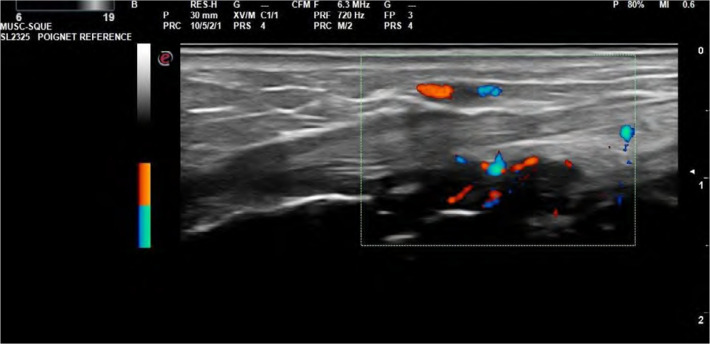

Abstract Image